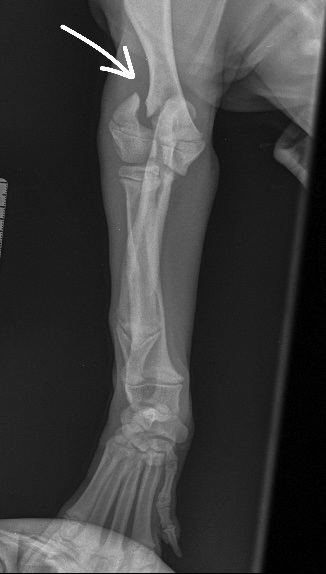

Otto is a gorgeous 14-week-old springer spaniel who very sadly broke his elbow.

This is actually quite a common fracture in young spaniels and is caused by the ‘growth plate’ of the elbow (where bones grow from in young animals) being a weak point within the joint. All Otto did was jump down from the sofa, and because of the exact force at the moment his foot hit the ground, the weight was transferred up his leg, into his elbow, through the soft growth plate and out of the side of the elbow – this is called a lateral condylar fracture.